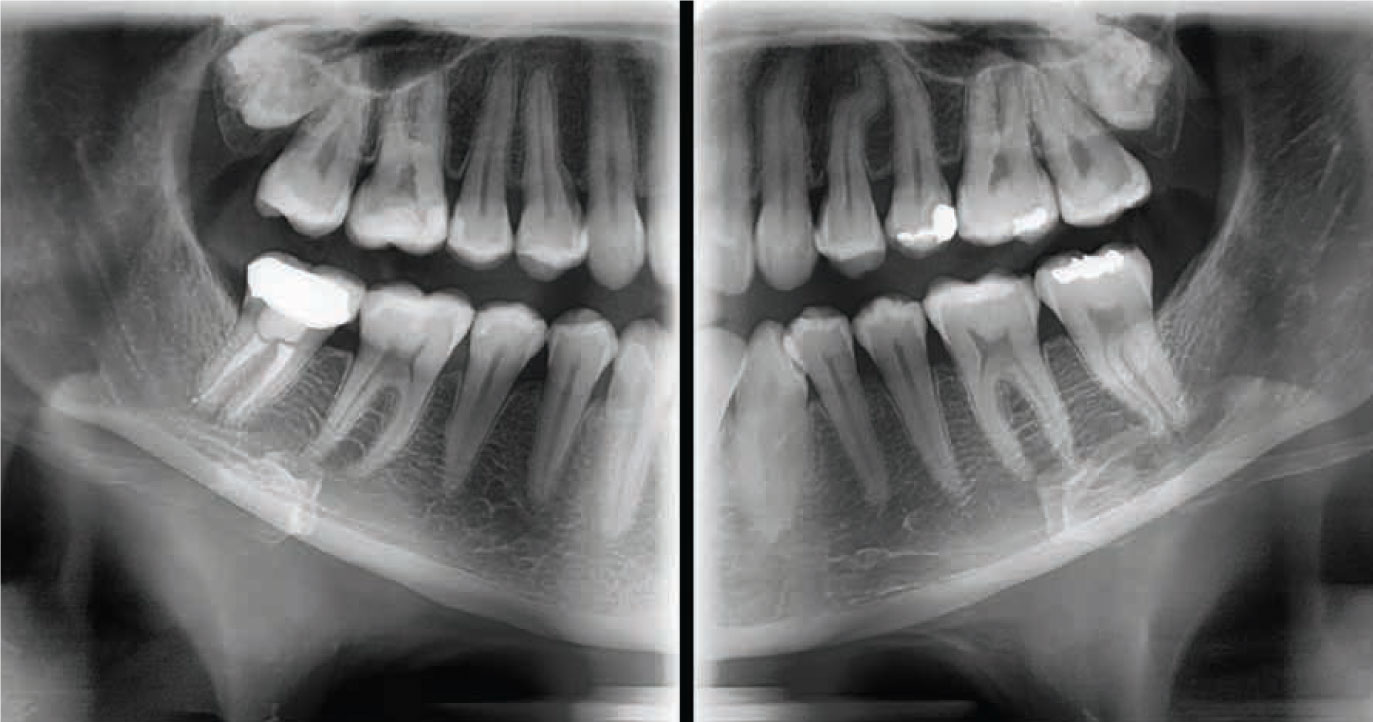

By combining image processing and accumulated experience in dental imaging, the PaX-i provides the most precise and high-quality panoramic images.

By combining image processing and accumulated experience in dental imaging, the PaX-i provides the most precise and high-quality panoramic images.

By combining image processing and accumulated experience in dental imaging, the PaX-i OPG provides the most precise and high-quality panoramic images.

SUPERIOR IMAGE QUALITY

– Optimal image for accurate diagnosis

By combining image processing and accumulated experience in dental imaging, the PaX-i OPG provides the most precise and high-quality panoramic images.

SUPERIOR IMAGE QUALITY

– Optimal image for accurate diagnosis

THE ADVANCED IMAGING SOLUTION FOR ACCURATE DENTAL DIAGNOSIS

The Pax-i OPG provides the most precise and high quality panoramic images by combining image processing and accumulated experience in dental imaging from Vatech. This will increase your diagnostic accuracy for improved treatment planning and patient satisfaction.

THE ADVANCED IMAGING SOLUTION FOR ACCURATE DENTAL DIAGNOSIS

The Pax-i OPG provides the most precise and high quality panoramic images by combining image processing and accumulated experience in dental imaging from Vatech. This will increase your diagnostic accuracy for improved treatment planning and patient satisfaction.